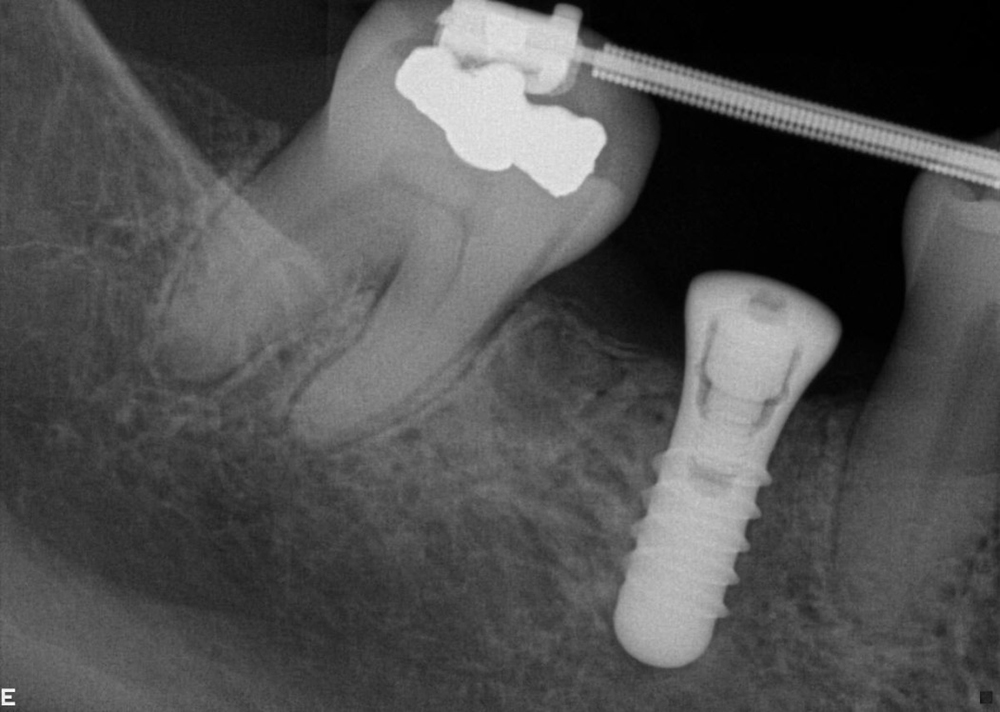

Our non-clinical goals in this case were to convey to the patient that her problems were an interdisciplinary, complex issue that had been ongoing and worsening for many years. Our solution to these problems would require the collaborative efforts of a team of dentists. The objective clinical goals were to orthodontically move her teeth into a less restrictive position and create room for restoration of lost tooth structure. Implants would be used not only to replace missing teeth but to provide orthodontic anchorage to facilitate movements that would not be possible with conventional orthodontics. Our final restorative goals were to reestablish ideal form and function, creating an occlusion that was stable and comfortable, enabling long term dental health. As her desires were specifically not to address esthetics, we were clear esthetic improvements were the result of correcting form and function. Of note is the fact that this case, from the restorative and surgical standpoint, was to be accomplished, with few small exceptions, entirely digitally.

Tooth no. 19 was isolated with a dental dam under local anesthesia. All existing restorative material and decay was excavated leaving a very evident crack into the pulp, down to the pulpal floor. The mesial canals were completely calcified, the decay extended beyond the bone level. This tooth was diagnosed as hopeless and scheduled for removal. A provisional was placed at this appointment.

Tooth no. 30 was deemed hopeless at initial evaluation and extracted.